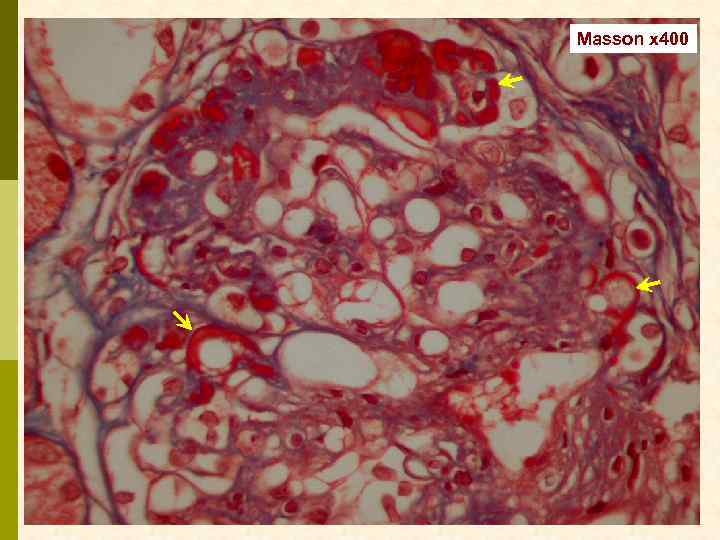

Masson x 400

Masson x 400

Masson x 400

Иммунофлюоресцентное исследование: p Клубочки: Ig. G (2+), Ig. M (3+), C 3 (2+), kappa (3+), lambda (1 -2+) - диффузная, субэндотелиальная и интракапиллярная, крупно-гранулярная экспрессия; p Стенки артериол: C 3 (2+); p Цилиндры: Ig. G (2+), Ig. A (3+), Ig. M (2+), C 3 (3+), kappa (3+), lambda (2+); p Реабсорбированные белковые капли: kappa (3+).

Предварительное гистологическое заключение: p Мембрано-пролиферативный, HCV-ассоциированный, криоглобулинемический(? ) гломерулонефрит с полным склерозом 47% клубочков, сегментарным склерозом 22% клубочков и формированием полулуний в 15% клубочков; p диффузно-очаговый выраженный острый канальцевый некроз; p выраженный артерио-артериолосклероз. Примечание: Криоглобулинемическая природа поражения будет уточняться при ЭМ-исследовании.